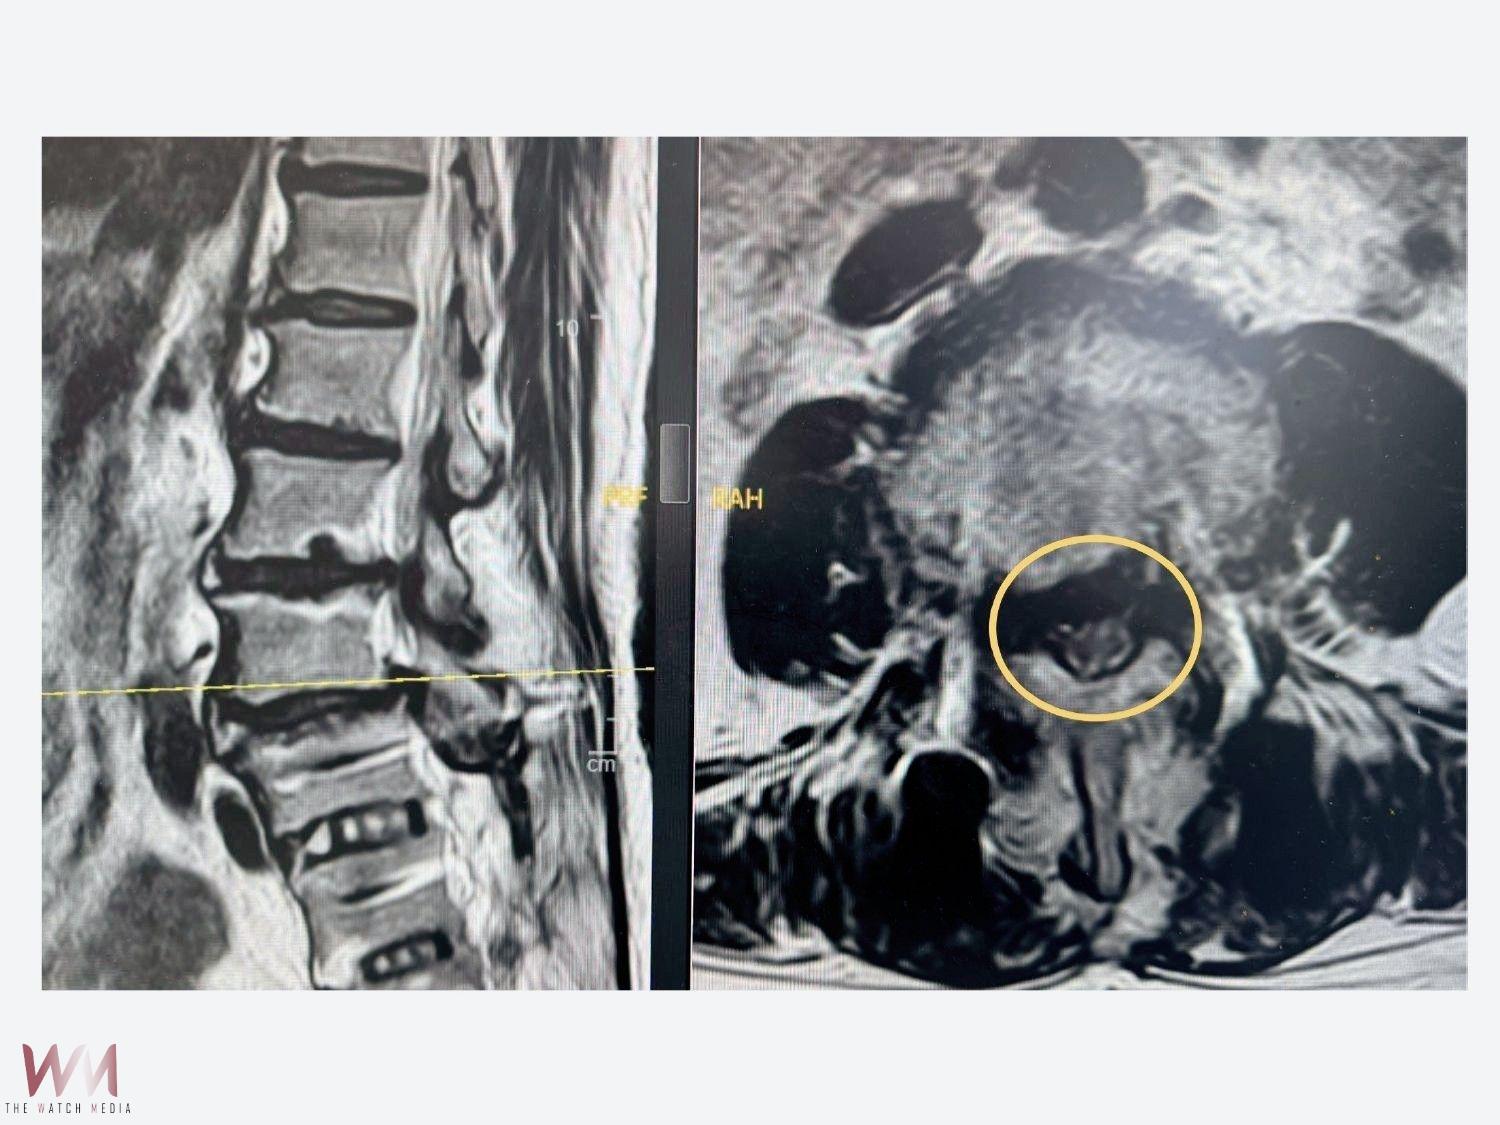

李建穎主任指出,由於林太太的「鄰近節脊椎狹窄症」並沒有脊椎不穩定的狀況,因此建議使用「微創脊椎內視鏡神經減壓手術」,僅在背部開一個0.8公分左右的小傷口,透過高解析度的內視鏡影像系統,手術器械便能精準移除林太太增生的骨頭、椎間盤和黃韌帶,解除神經的壓迫。由於高解析度的內視鏡影像系統可以清楚放大手術影像,有效減少出血量和避免正常組織受損,降低手術併發症和後遺症的風險。